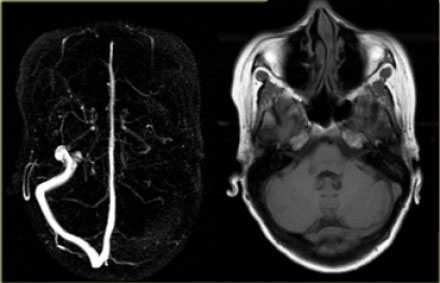

МРТ головного мозга: справа (зеленая стрелка) на Т2-взвешенном изображении отмечается имеющийся в норме феномен «пустоты потока» от правого сигмовидного синуса и яремной Вены. Слева (оранжевая стрелка) отмечается аномально высокий сигнал, в результате, вероятнее, тромбоза. Для подтверждения синус-тромбоза и окончательного определения локализации и протяженности тромбоза необходимо проведение МР-венографии.

МР-венография: тромбоз левого поперечного синуса. Отмечается потеря МР-сигнала от левого поперечного синуса.

Наличие визуализации синуса на «сырых» данных или же МРТ головного мозга подтверждает тромбоз синуса и исключает его гипоплазию.

МР-венография: тромбоз правого поперечного синуса. Отмечается потеря МР-сигнала от правого поперечного синуса.

Наличие визуализации синуса на «сырых» данных или же МРТ головного мозга подтверждает тромбоз синуса и исключает его гипо- и аплазию.

Тромбоз правого поперечного синуса. Отсутствие феномена «пустоты потока» от правого поперечного синуса на МРТ головного мозга. Отсутствие визуализации правого поперечного синуса на МР-венографии.